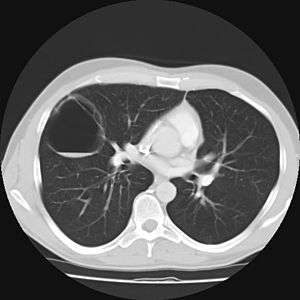

Imaging

The earliest point at which a CPAM can be detected is by prenatal ultrasound. The classic description is of an echogenic lung mass that gradually disappears over subsequent ultrasounds. The disappearance is due to the malformation becoming filled with fluid over the course of the gestation, allowing the ultrasound waves to penetrate it more easily and rendering it invisible on sonographic imaging. When a CPAM is rapidly growing, either solid or with a dominant cyst, they have a higher incidence of developing venous outflow obstruction, cardiac failure and ultimately hydrops fetalis. If hydrops is not present, the fetus has a 95% chance of survival. When hydrops is present, risk of fetal demise is much greater without in utero surgery to correct the pathophysiology. The greatest period of growth is during the end of the second trimester, between 20–26 weeks.

A measure of mass volume divided by head circumference, termed cystic adenomatoid malformation volume ratio (CVR) has been developed to predict the risk of hydrops. The lung mass volume is determined using the formula (length × width × anteroposterior diameter ÷ 2), divided by head circumference. With a CVR greater than 1.6 being considered high risk. Fetuses with a CVR less than 1.6 and without a dominant cyst have less than a 3% risk of hydrops. After delivery, if the patient is symptomatic, resection is mandated. If the infant is asymptomatic, the need for resection is a subject of debate, though it is usually recommended. Development of recurrent infections, rhabdomyosarcoma, adenocarcinomas in situ within the lung malformation have been reported.[4]